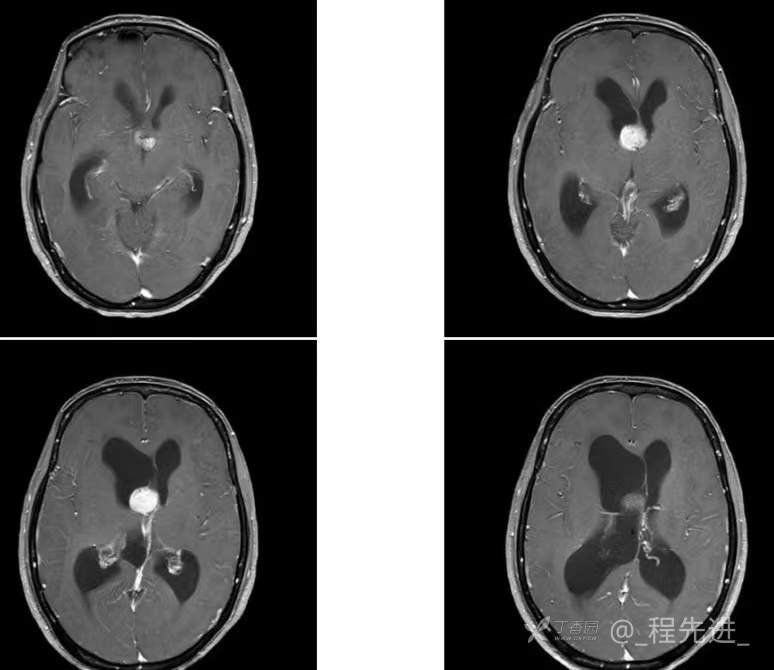

患者性别:女

患者年龄:55岁

简要病史:头痛头晕4年余,无明显诱因,10余年前因“输卵管破裂大出血”手术治疗

脑膜瘤 (78)

过渡型(混合性)脑膜瘤 (1)